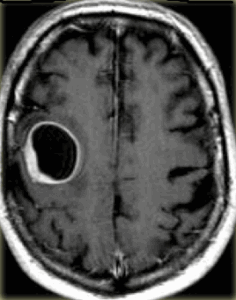

Центральная нейроцитома - кистозно-солидное объёмное образование, расположенное в боковом желудочке, связанное с прозрачной перегородкой, сопровождающееся расширением желудочковой системы (рис.677, 678).

На КТ и МРТ нейроцитомы - отграниченные образования, смешанной плотности, часто содержат кальцинаты (в 50-70% случаев) и кисты. В большинстве случаев опухоль сопровождается гидроцефалией обструктивного генеза.

Опухоль может инфильтрировать стенку бокового желудочка. В 20% случаев имеются внутриопухолевые кровоизлияния. Располагаются в просвете боковых желудочков головного мозга с тенденцией к локализации в области прозрачной перегородки и отверстия Монро.

Центральная нейроцитома в виде неоднородной структуры объёмного образования, расположенного в боковом желудочке, связанное с прозрачной перегородкой (звёздочки на рис.679-681), сопровождающееся расширением бокового желудочка (головки стрелок на рис.680, 681). МРТ демонстрирует врастание опухоли в стенку бокового желудочка левого полушария большого мозга (стрелки на рис.680, 681).